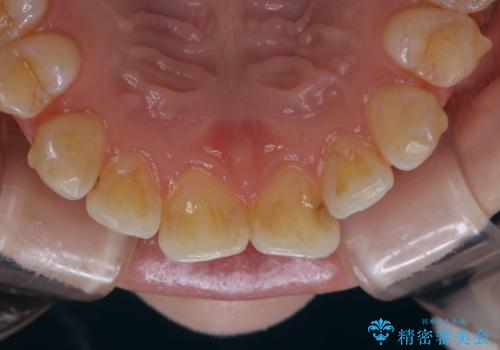

インビザラインでの治療中の患者様のクリーニング前後写真です。

- インビザライン矯正中に茶色が気になるとのことで来院されました。PMTC30分コースを行いました。